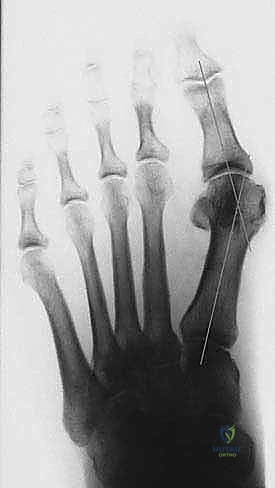

يقوم الدكتور هطيف بقياس زوايا محددة:

* زاوية إبهام القدم الأروح (HVA): الزاوية بين عظم المشط الأول والإصبع الكبير.

* الزاوية بين الأمشاط (IMA): الزاوية بين عظم المشط الأول والثاني.

بناءً على هذه الزوايا، يتم تصنيف الحالة إلى خفيفة، متوسطة، أو شديدة. جراحة (ماو) تُخصص عادة للحالات المتوسطة إلى الشديدة التي تتطلب تصحيحاً كبيراً ومستقراً.